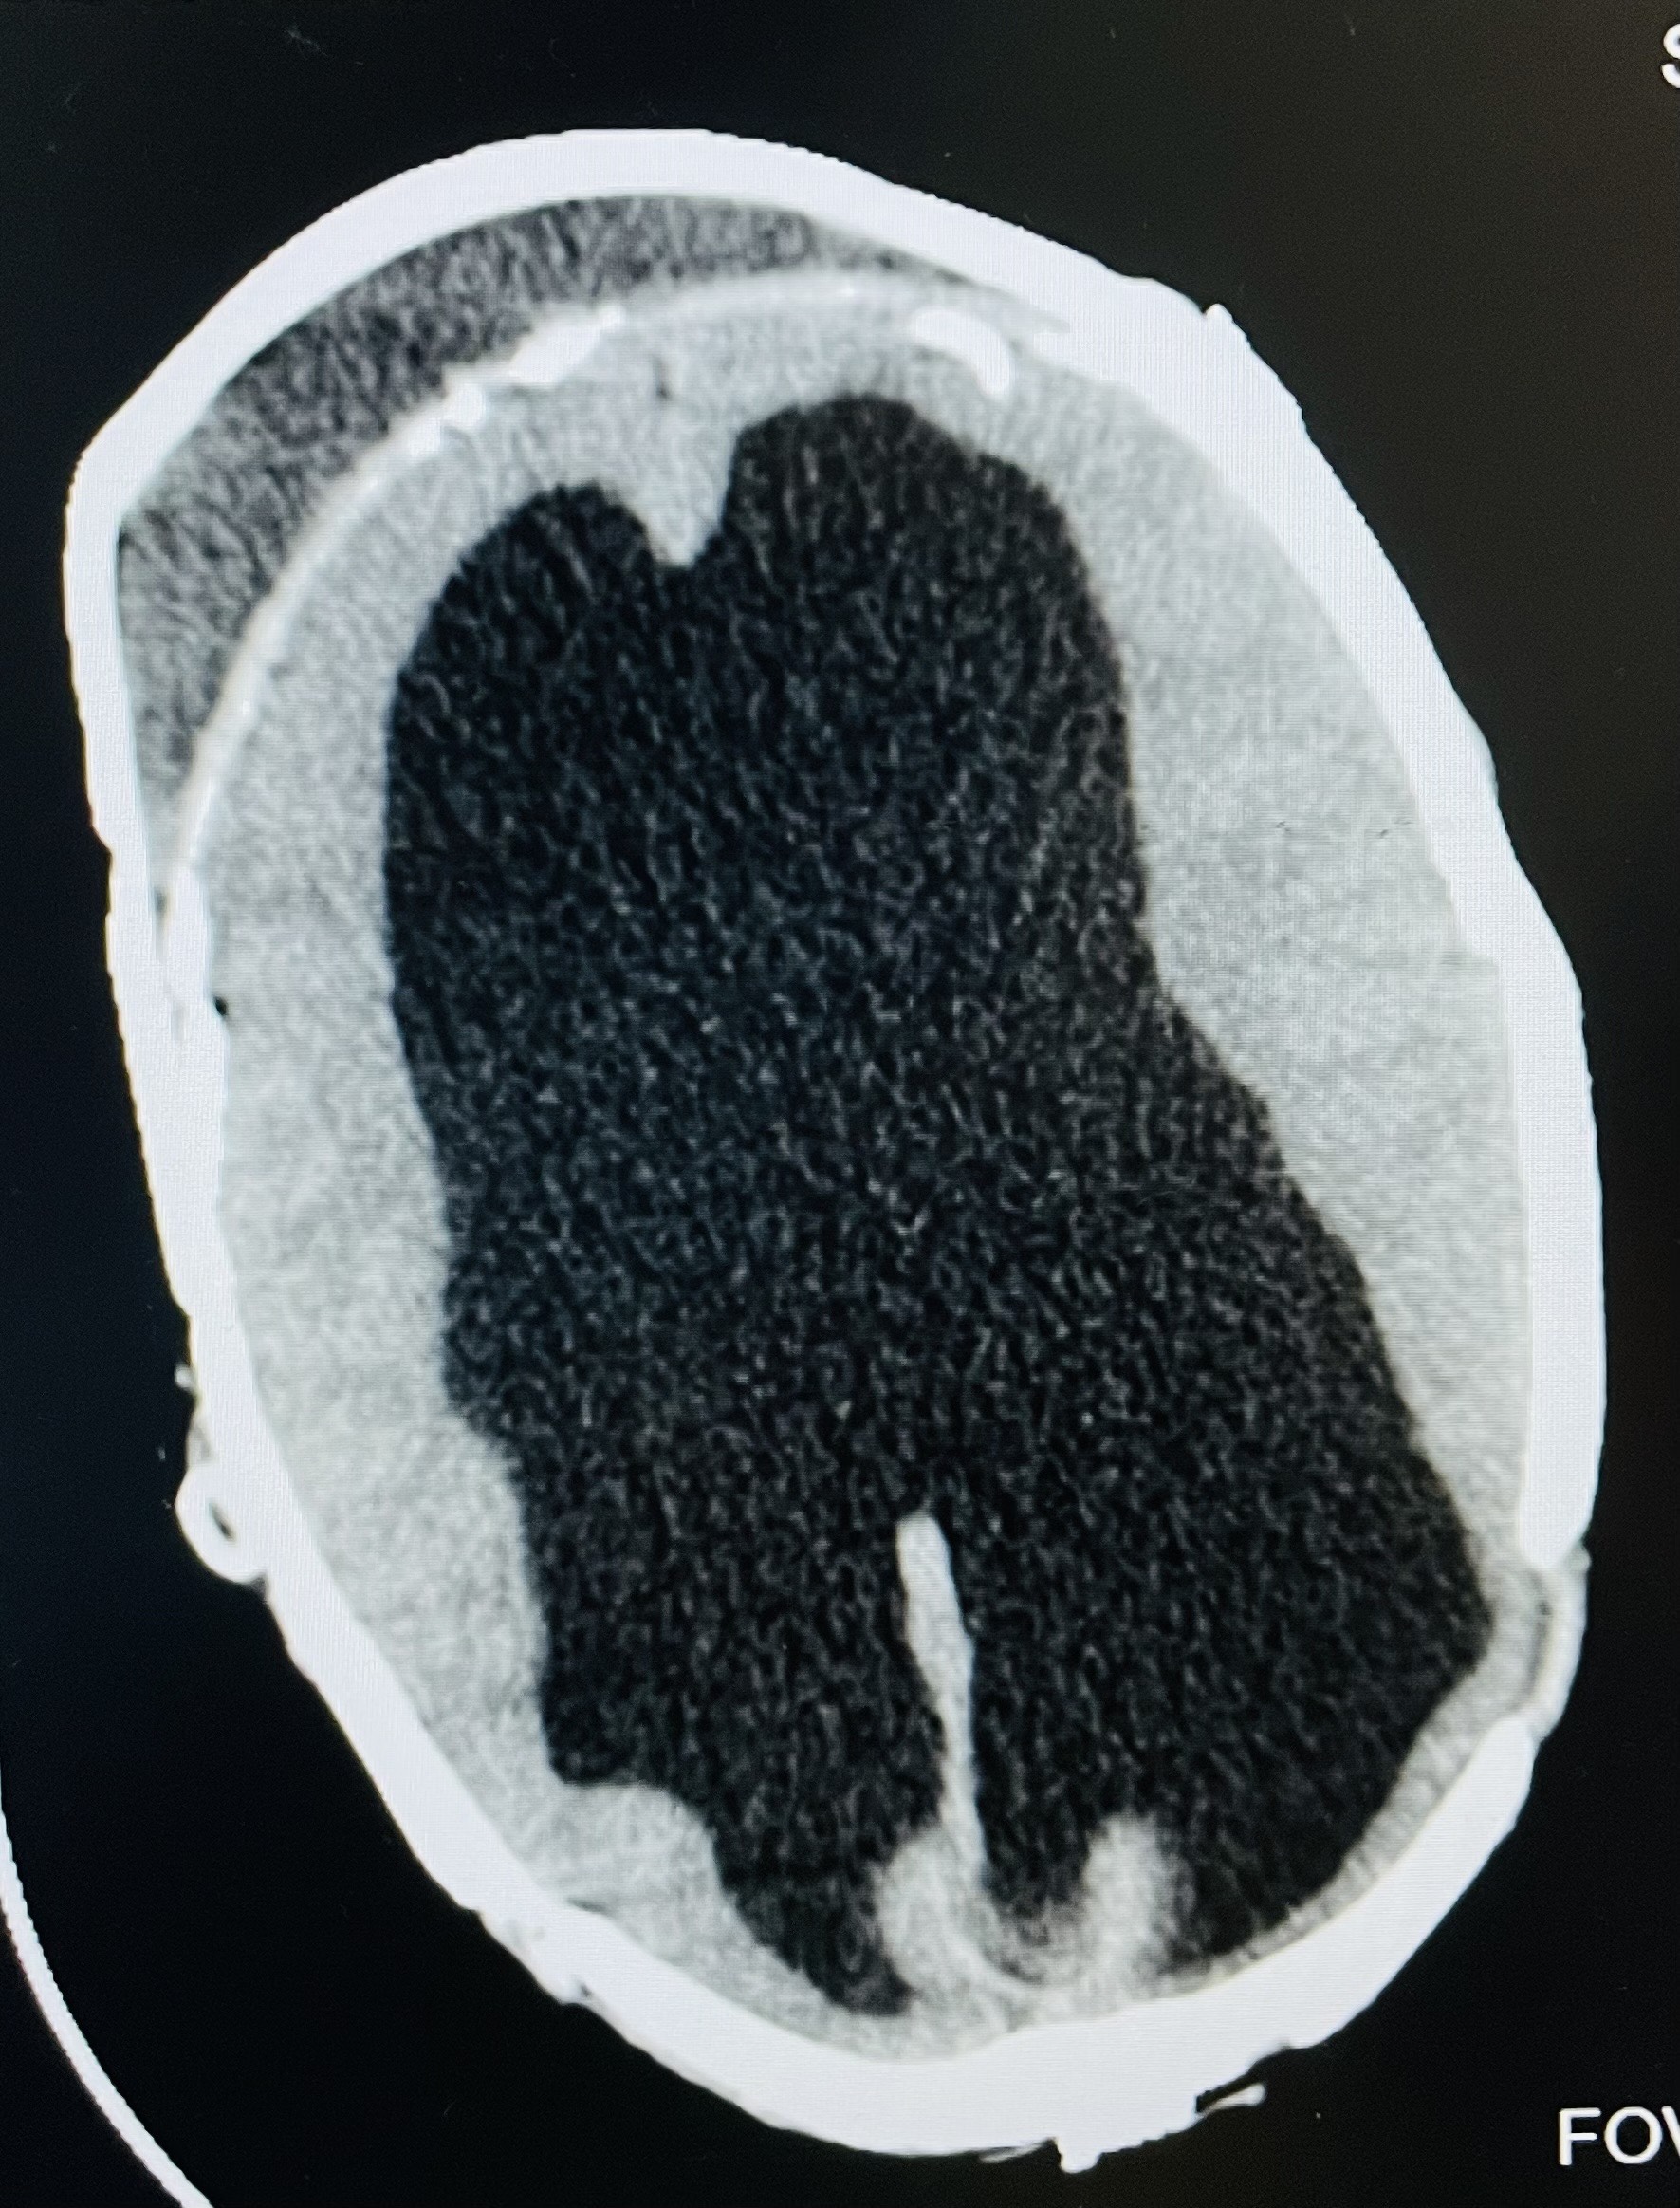

Successful Staged Macrocephaly Reduction Surgery in SriLanka

Related Article : Successful Staged Macrocephaly Reduction Surgery in SriLanka